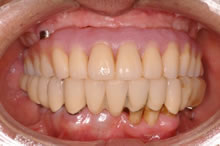

【3】治療経過写真(上アゴに仮歯が入りました。)

残りのインプラント2本も揺れていました。 CT検査の結果により、左右上奥のインプラントを支える骨が不足していました。そのため、揺れているインプラント撤去と同時に、支えるの骨を増やす特殊な手術、上顎洞底挙上術(サイナスリフト)を併用し、じっくり治療していけばインプラント治療が可能になることを説明しました。ご本人も術後の回復された後の状態がイメージでき、治療を希望され開始しました。 現在、丈夫な骨を再建する特殊な治療もインプラント6本を埋入終了し、仮歯を装着して美味しく食事をされています。 今後、下アゴにも15年以上前に入れてご自分の歯と連結されていますが揺れている経過が危ういインプラントがあるため、撤去し、再度、インプラントを予定しています。